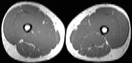

Visible Human male: Sectio transversalis 2093

CT

NMR

Pd                          / T2 \                         T1